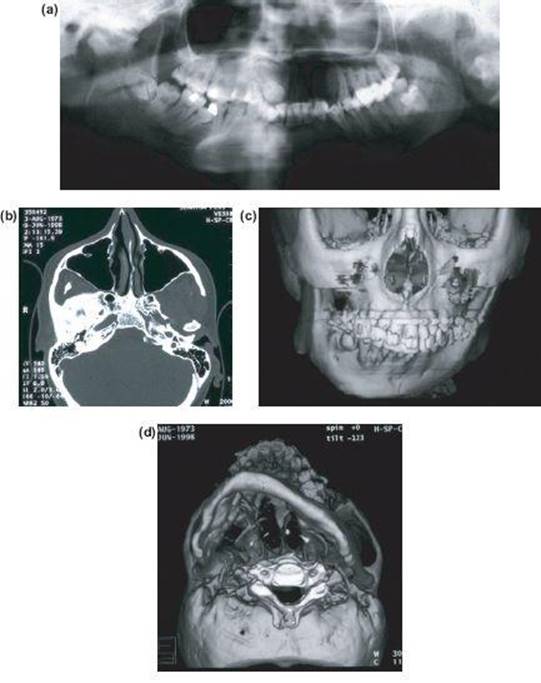

Figure 13.5 Imaging showing (a) apparent fibrosseous ankylosis of right TMJ but (b) shows complete fusion with base of skull. (c) 3D CT shows straight ankylosis side with deformed growing contralateral side with occlussal cant and (d) lower border of mandible shows impaired growth in all dimensions (case of Kieren Coghlin).

Preoperative Imaging (Figure 13.5)

• OPG.

• True lateral skull.

• CT scan with 3D reconstruction.

• Standard orthognathic photographic series.